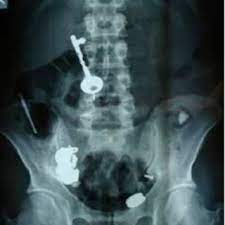

Kazayla Giren Nesneler

O Şişe Oraya Bakın Nasıl Girmiş…Röntgen filmlerinden çıkan akılalmaz şeyler Röntgen filmlerinden “akıl almaz şeyler Hastane koridorlarına düşenler bilir…